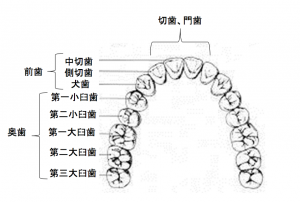

では、歯科の世界はどうでしょうか?

何科があるかご存知でしょうか?

歯科、口腔外科、矯正科、小児歯科はよく診療所に書いてあるのを見るかと思います。

でも標榜はしてはいけなくても例えば大学なら実はたくさんの科があります。

歯周病科、保存科、インプラント科、補綴科、放射線科、歯科麻酔科、歯内療法科、

そしてマタニティー歯科、いびき科という科まであったりします。